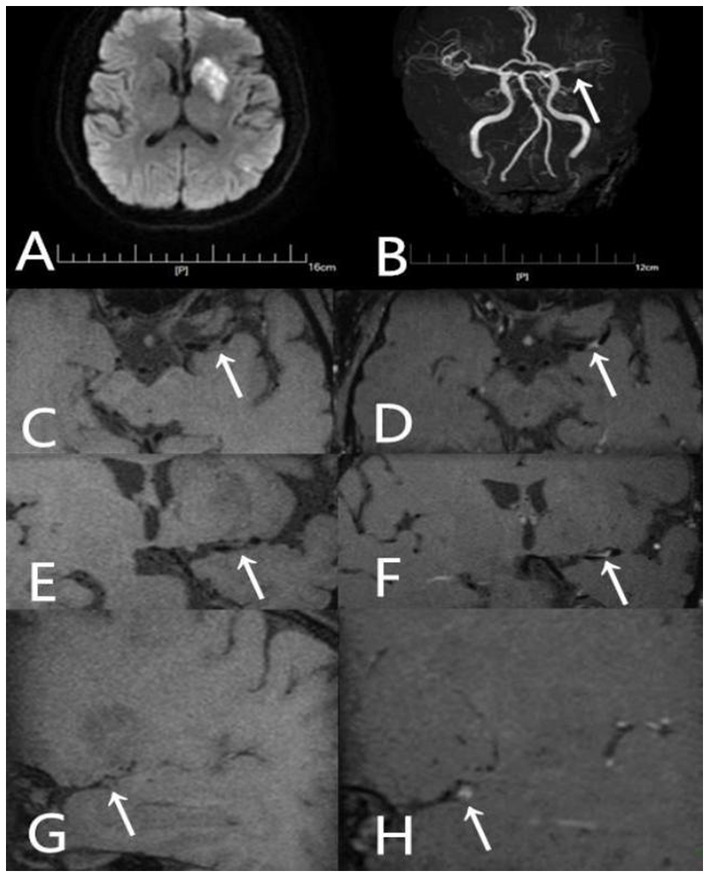

A 54-year-old male presented with aphasia and right-sided hemiparesis of one day’s duration. He had not been taking any statin medication prior to the onset. (A) DWI shows high signal intensity lesions in the left fronto-parieto-insular region and basal ganglia. (B) TOF-MRA demonstrates severe stenosis in the left middle cerebral artery (arrow). (C) Axial T1-weighted pre-contrast image shows the plaque (arrow). (D) Axial T1-weighted post-contrast image demonstrates eccentric wall thickening of the plaque (arrow) with enhancement. (E) Coronal T1-weighted pre-contrast image shows the plaque (arrow). (F) Coronal T1-weighted post-contrast image demonstrates eccentric wall thickening of the plaque (arrow) with enhancement. (G) Sagittal T1-weighted pre-contrast image shows the plaque (arrow). (H) Sagittal T1-weighted post-contrast image demonstrates eccentric wall thickening of the plaque (arrow) with enhancement.